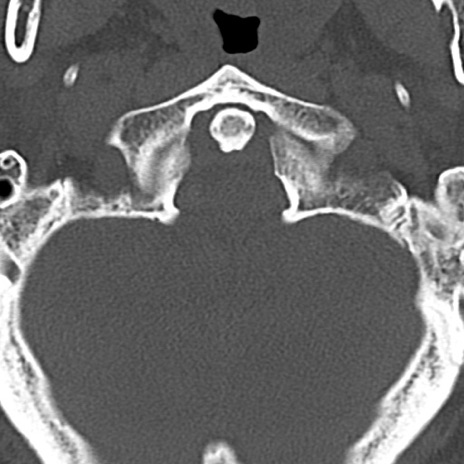

頚椎CT

横断像